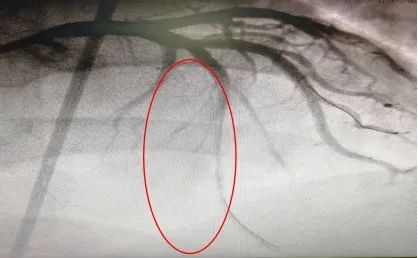

开通血管后造影图像

术中,何鹏程教授细致阅读对侧造影影像,在密密麻麻细小的侧支血管中,快速精准选择好合适的侧支入路,导丝逆向通过慢性闭塞病变顺利送达正向指引导管,成功开通闭塞血管。经冠状动脉介入术后次日,患者病情稳定办理出院。